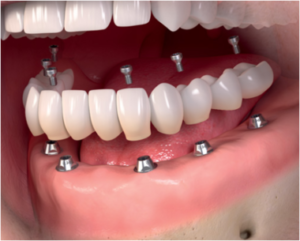

Які варіанти протезування існують при адентії – повній відсутності зубів? Найбільш надійний і ефективний як з функціональної, так і з естетичної точки зору, варіант протезування – установка «незнімніка» на 6-8 імплантатах (класичний варіант – на 8 імплантатах, більш економічний – «All-on-6» – на 6 імплантатах) . Існує також технологія протезування за технологією «All-on-4» ( «все на 4»), коли в якості опори для протеза використовується всього 4 імпланта. На них можна встановити як знімний, так і незнімний протез, хоча, звичайно ж, конструкція «незнімніка» на 4 опорах буде менш надійною і стабільною, ніж на 6 або 8. Існує також надекономічний варіант знімного протезування – всього лише на 2-3 імплантатах , їх буде цілком достатньо для надійної фіксації «знімача».

Повние протезування зубів на імплантатах здійснюється класичним методом установки дентальних імплантів, як опори майбутнього протеза, це забезпечує надійність кріплення і гарантує максимально тривале збереження протезної конструкції, що збільшує період її експлуатації в справному стані під дією щоденних фізичних навантажень.

Для незнімного повного протезування зубів на імплантатах потрібно встановити від 6 до 8 імплантів – опор. При необхідності проводиться аугментація (нарощування) кісткової тканини ( синус – ліфтинг ) в окремих передбачуваних ділянках імплантації імплантів.